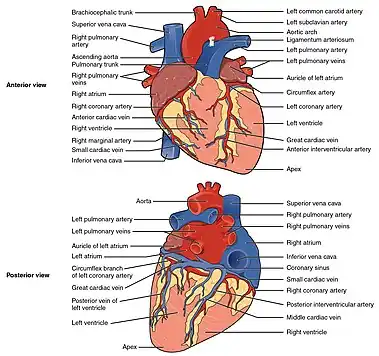

The heart has four chambers, two upper atria, the receiving chambers, and two lower ventricles, the discharging chambers. The atria open into the ventricles via the atrioventricular valves, present in the atrioventricular septum. This distinction is visible also on the surface of the heart as the coronary sulcus.[20] There is an ear-shaped structure in the upper right atrium called the right atrial appendage, or auricle, and another in the upper left atrium, the left atrial appendage.[21] The right atrium and the right ventricle together are sometimes referred to as the right heart. Similarly, the left atrium and the left ventricle together are sometimes referred to as the left heart.[6] The ventricles are separated from each other by the interventricular septum, visible on the surface of the heart as the anterior longitudinal sulcus and the posterior interventricular sulcus.[20]

Heart tissue receives blood from two arteries which arise just above the aortic valve. These are the left main coronary artery and the right coronary artery. The left main coronary artery splits shortly after leaving the aorta into two vessels, the left anterior descending and the left circumflex artery. The left anterior descending artery supplies heart tissue and the front, outer side, and septum of the left ventricle. It does this by branching into smaller arteries—diagonal and septal branches. The left circumflex supplies the back and underneath of the left ventricle. The right coronary artery supplies the right atrium, right ventricle, and lower posterior sections of the left ventricle. The right coronary artery also supplies blood to the atrioventricular node (in about 90% of people) and the sinoatrial node (in about 60% of people). The right coronary artery runs in a groove at the back of the heart and the left anterior descending artery runs in a groove at the front. There is significant variation between people in the anatomy of the arteries that supply the heart [32] The arteries divide at their furthest reaches into smaller branches that join at the edges of each arterial distribution.[7]

The coronary sinus is a large vein that drains into the right atrium, and receives most of the venous drainage of the heart. It receives blood from the great cardiac vein (receiving the left atrium and both ventricles), the posterior cardiac vein (draining the back of the left ventricle), the middle cardiac vein (draining the bottom of the left and right ventricles), and small cardiac veins.[33] The anterior cardiac veins drain the front of the right ventricle and drain directly into the right atrium.[7]

The right heart collects deoxygenated blood from two large veins, the superior and inferior venae cavae. Blood collects in the right and left atrium continuously.[7] The superior vena cava drains blood from above the diaphragm and empties into the upper back part of the right atrium. The inferior vena cava drains the blood from below the diaphragm and empties into the back part of the atrium below the opening for the superior vena cava. Immediately above and to the middle of the opening of the inferior vena cava is the opening of the thin-walled coronary sinus.[7] Additionally, the coronary sinus returns deoxygenated blood from the myocardium to the right atrium. The blood collects in the right atrium. When the right atrium contracts, the blood is pumped through the tricuspid valve into the right ventricle. As the right ventricle contracts, the tricuspid valve closes and the blood is pumped into the pulmonary trunk through the pulmonary valve. The pulmonary trunk divides into pulmonary arteries and progressively smaller arteries throughout the lungs, until it reaches capillaries. As these pass by alveoli carbon dioxide is exchanged for oxygen. This happens through the passive process of diffusion.

In the left heart, oxygenated blood is returned to the left atrium via the pulmonary veins. It is then pumped into the left ventricle through the mitral valve and into the aorta through the aortic valve for systemic circulation. The aorta is a large artery that branches into many smaller arteries, arterioles, and ultimately capillaries. In the capillaries, oxygen and nutrients from blood are supplied to body cells for metabolism, and exchanged for carbon dioxide and waste products.[7] Capillary blood, now deoxygenated, travels into venules and veins that ultimately collect in the superior and inferior vena cavae, and into the right heart.